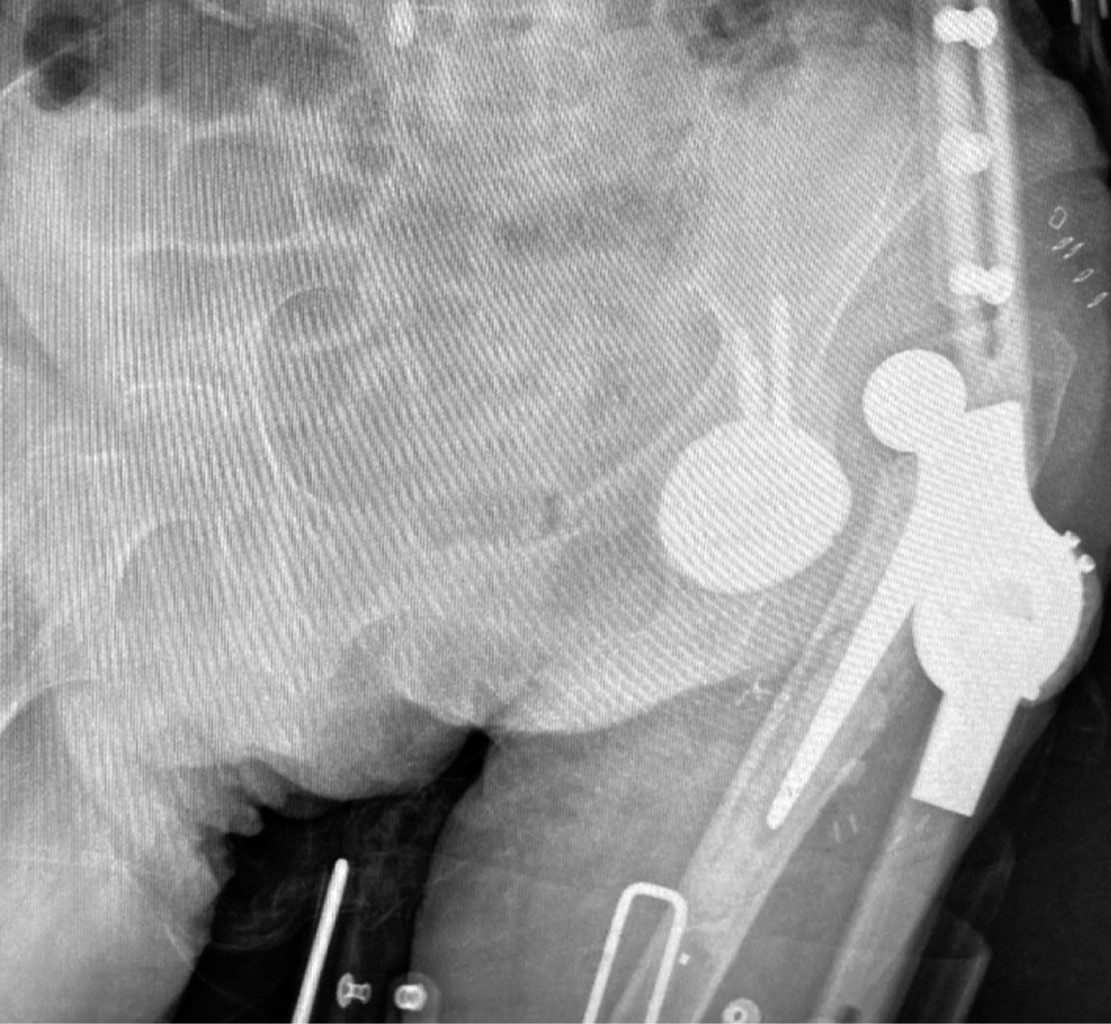

En el grupo DM se necesitó la utilización de aloinjerto de esponjosa de cabeza femoral en 60% de la muestra para el relleno del defecto acetabular presente; mientras que en el grupo M se precisó del mismo aloinjerto en 56.7% de los casos (Figura 1).

En cuanto a la incidencia de complicaciones, en el grupo M fue de 6.7% y en el grupo DM de 13.2% sin ser estas diferencias significativas (p > 0.05); de las cuales en el grupo M obtuvimos un caso de luxación posterior (3.3%) que se resolvió mediante reducción cerrada en quirófano y tratamiento conservador (Figura 3); y un caso de infección protésica precoz (3.3%) que se resolvió mediante limpieza quirúrgica. En cambio, en el grupo DM encontramos tres casos de luxación protésica posterior (9.9%) que se resolvieron mediante el cambio del polietileno, aportando una ceja posterosuperior de mayor tamaño; y un caso (3.3%) de infección protésica precoz que se resolvió mediante limpieza quirúrgica.